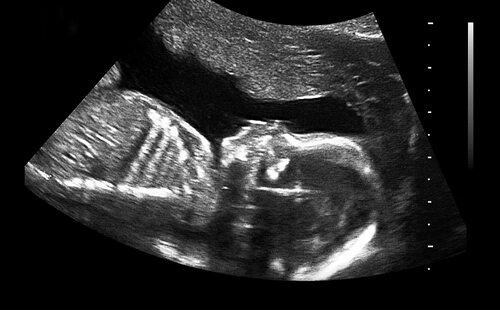

В данной статье представлено множество фотографий, которые иллюстрируют процесс УЗИ 2 скрининга и его результаты. На фотографиях можно увидеть изображения плода, его органов и систем, а также возможные патологии и аномалии развития.

Фотографии УЗИ 2 скрининга помогут вам визуально представить, как проходит данная процедура и что можно обнаружить при диагностике плода. Будьте внимательны и обратитесь к специалисту, если у вас возникнут вопросы или беспокойства.